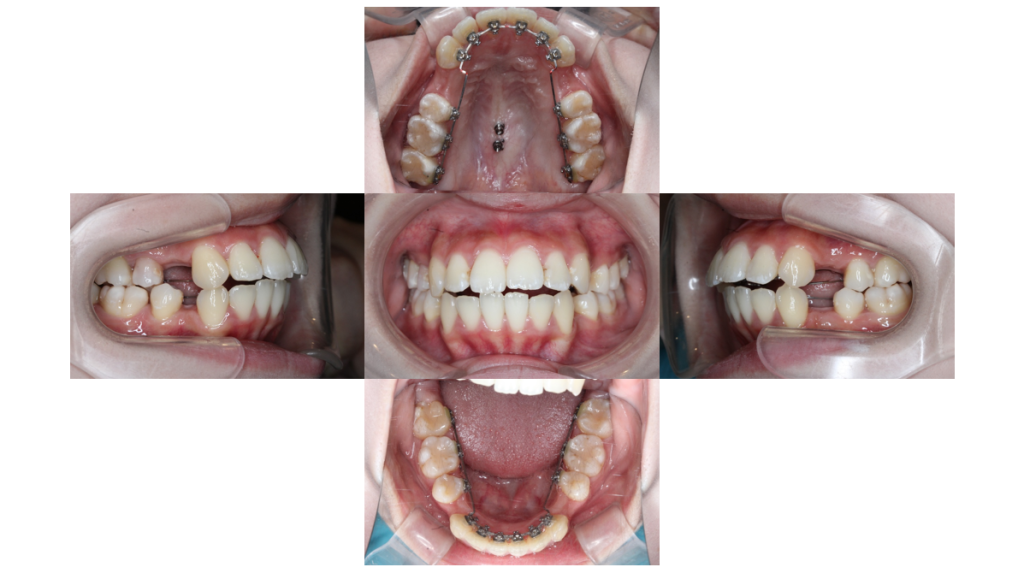

8ヶ月経過

叢生・裏側矯正の症例前歯の隙間が閉じ、きれいなアーチに近づいてきました。

アンカースクリュー埋入

叢生・裏側矯正の症例抜歯窩のスペースクローズに使用するアンカースクリューを上顎に埋入しました。